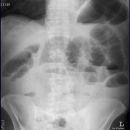

Abdomen

Ileus